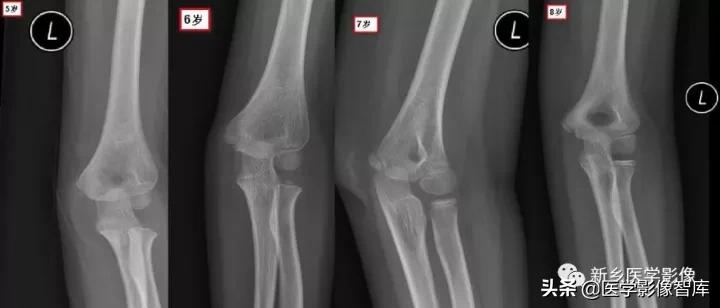

现在简单了,只要记住CRI TOE1-3-5-7-9-11就行了:

- Capitellum (appears age 1-2)肱骨小头1 year - Radial Head (appears age 2-4)桡骨小头 3years- Interanal epicondyle (appears age 4-6)内上髁 5years- Trochlea (appears age 8-11)滑车 7years- Olecranon (9-11 years)鹰嘴 9years- External epicondyle (appears age 10-11)外上髁 11years